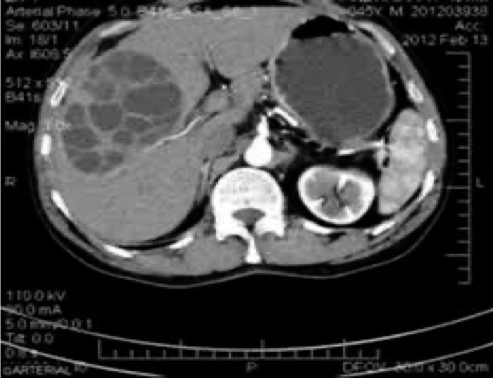

ultrasound and CT scan can show the site, size and daughter cyst in the liver

Hydatid cyst (multiple daughter cyst) in the right lobe of the liver